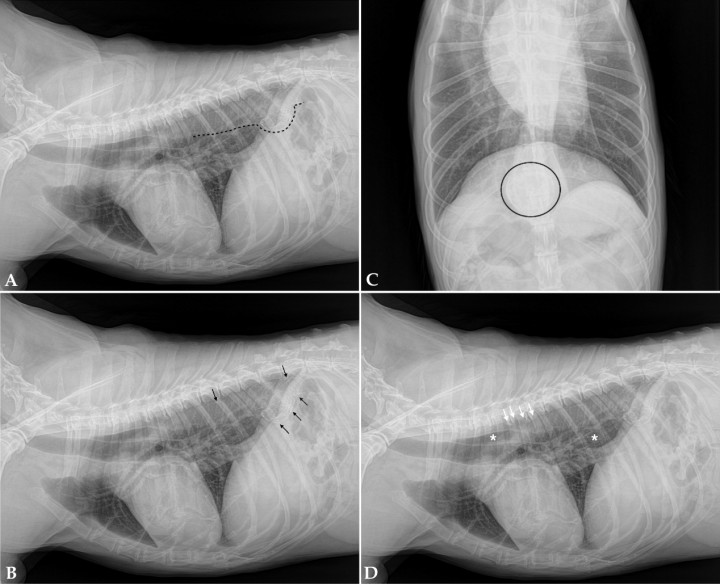

Se refiere al hospital una perra mestiza hembra esterilizada, de 13 años, con historia de vómitos y regurgitaciones esporádicas, de un mes y medio de evolución. Tanto el examen físico como la analítica sanguínea fueron normales sin revelar ninguna alteración. Se realizó un estudio radiográfico torácico para la evaluación del esófago incluyendo dos proyecciones: lateral derecha y ventrodorsal (Fig. 1).

<p>Radiografías de tórax de un perro con vómitos y regurgitaciones esporádicas de un mes y medio de evolución. (<strong>A</strong>) Proyección lateral derecha. (<strong>B</strong>) Proyección ventrodorsal.</p>

Figura 1

Radiografías de tórax de un perro con vómitos y regurgitaciones esporádicas de un mes y medio de evolución. (A) Proyección lateral derecha. (B) Proyección ventrodorsal.

Se observa una dilatación de la aorta intratorácica caudal con presencia de múltiples focos de mineralización distrófica en su pared, comprendidos entre la T8-T12. Ventral a T11 se evidencia otra estructura de morfología redondeada circunferencial con mineralización marcada de su pared. El esófago intratorácico presenta discreta dilatación con aire en su luz. La silueta cardíaca presenta disminución de su volumen. En la columna se evidencia espondilosis marcada en T4, T5, T6 (Fig. 2).

<p style=\"text-align:justify\">Mismas imágenes que Figura 1. (<strong>A</strong>, <strong>B</strong>) Se observa dilatación de la aorta intratorácica caudal (línea negra discontinua) con focos de mineralización distrófica en su pared entre la T8-T12 (flechas negras). (<strong>C</strong>) Ventral a T11 se evidencia una estructura circunferencial con mineralización de su pared (área delimitada en negro). (<strong>D</strong>) El esófago intratorácico presenta discreta dilatación con aire en su luz (asterisco blanco). Las flechas blancas señalan la espondilosis más marcada en T4, T5, T6.</p>

Figura 2

Mismas imágenes que Figura 1. (A, B) Se observa dilatación de la aorta intratorácica caudal (línea negra discontinua) con focos de mineralización distrófica en su pared entre la T8-T12 (flechas negras). (C) Ventral a T11 se evidencia una estructura circunferencial con mineralización de su pared (área delimitada en negro). (D) El esófago intratorácico presenta discreta dilatación con aire en su luz (asterisco blanco). Las flechas blancas señalan la espondilosis más marcada en T4, T5, T6.